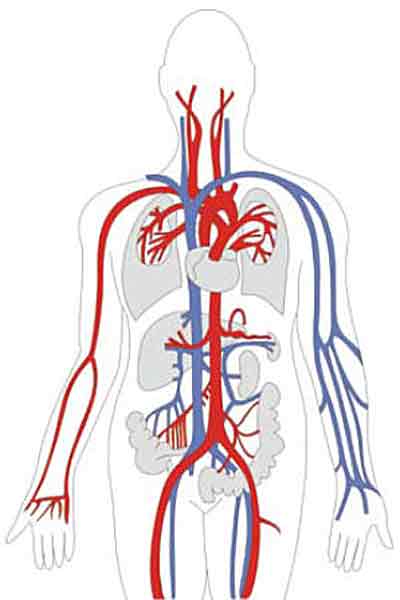

Проявления этого заболевания могут значительно различаться в зависимости от места расположения источника осложнения. В связи с этим и симптомы могут быть весьма разнообразными. Локализация проблемы может быть отчетливо выраженной, и среди основных зон риска можно выделить:

- сосуды глаз;

- сосуды верхних и нижних конечностей;

- сосуды почек;

- сосуды сердца.

Если рассмотреть более детально причины на уровне функционирования организма, то диабетическая ангиопатия возникает из-за сужения мелких артериальных сосудов, расположенных рядом с различными клетками организма.

Этот тип называется микроангиопатией. Альтернативное проявление – макроангиопатия, которая развивается при атеросклеротическом поражении более крупных сосудов.